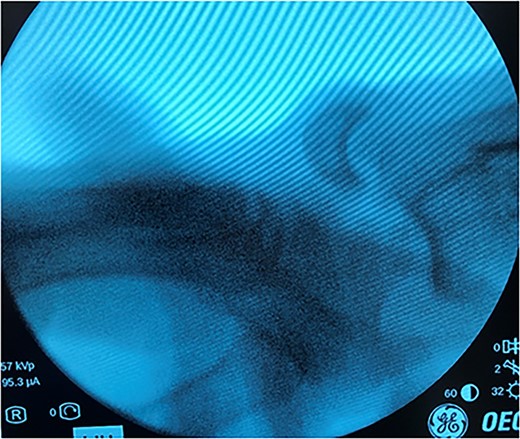

An unhelmeted 59-year-old male presented to the trauma bay at our institution after being involved in a motorcycle accident. This polytraumatized patient had been intubated prior to arrival and evaluation revealed numerous orthopedic injuries, including a right dorsal lunate dislocation (Fig. 1). Other injuries included a left distal femur fracture, left superior and inferior rami fractures, left APC II pelvic ring fracture, left closed tibia/fibula fractures, a Type III open right tibial shaft fracture, a right anterior column acetabulum fracture, and a Type I open right distal radius fracture. Traumatic subarachnoid hemorrhage to the bilateral frontal lobes, a unilateral occipital condyle fracture, a C1 fracture posterior arch fracture, a craniocervical dislocation, and numerous rib fractures were also noted. In addition to splinting all other peripheral injuries, the right distal radius fracture and lunate dislocation were closed reduced using a sugartong splint, with the wrist positioned in slight extension (Fig. 2).

Anteroposterior (AP) and lateral views demonstrating the right distal radius and perilunate dislocation after closed reduction in the trauma bay.